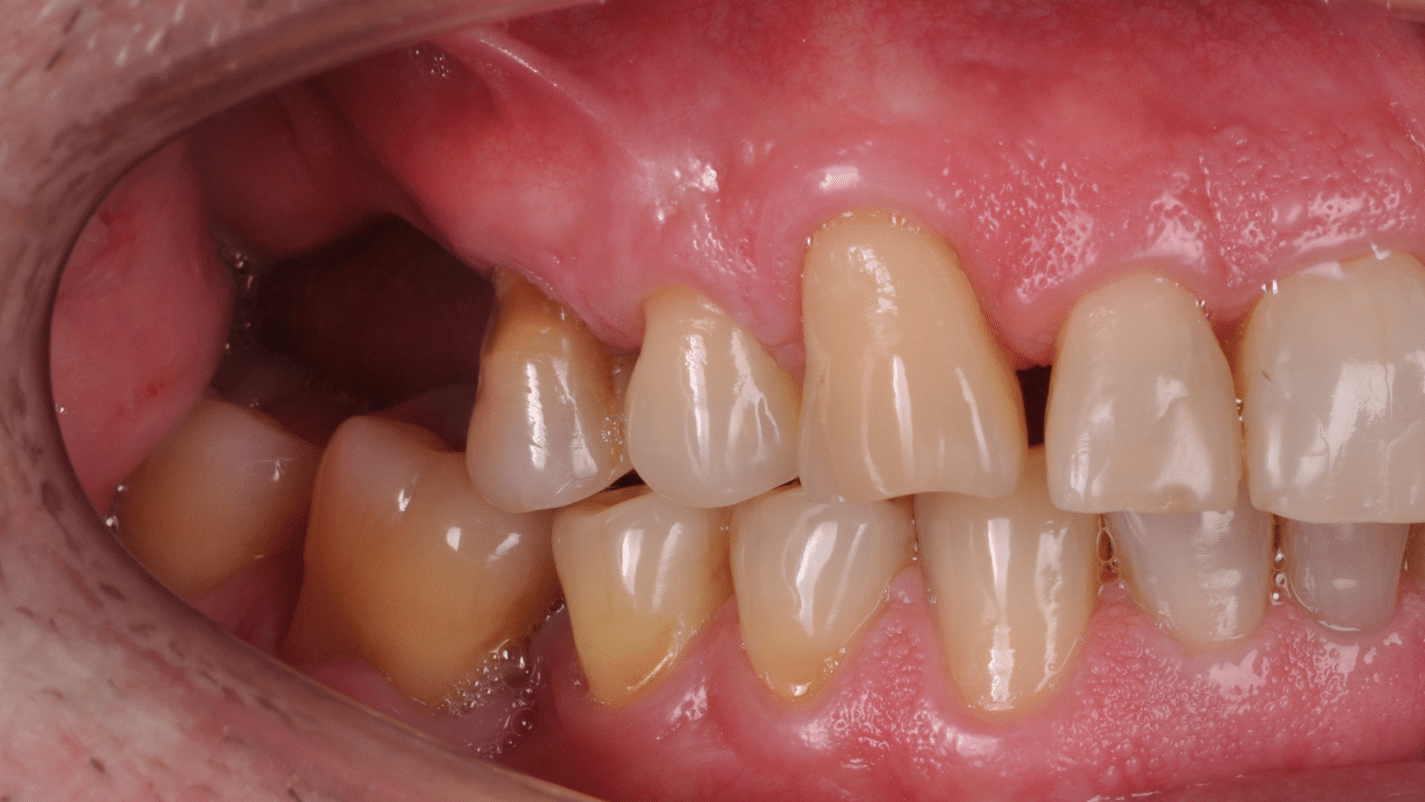

Împreună cu pacientul, am optat pentru inserarea implantelor cu ajutorul ghidului chirurgical pentru a plasa implantul în poziția protetică ideală și pentru a permite realizarea coroanelor insurubate pe implant. A fost efectuată scanarea digitală a arcadelor și a ocluziei pacientului, iar împreună cu tehnicianul radiolog de la DigiRay a fost suprapus fișierul .stl al amprentei digitale peste fișierul .dcm de la CBCT, utilizând software-ul 3Shape.

S-a planificat individual poziția și axul de inserție al fiecărui implant.

Doar astfel putem crea profilul de emergență corect al coroanei dentare, ceea ce permite conformarea papilei și a sulcusului.